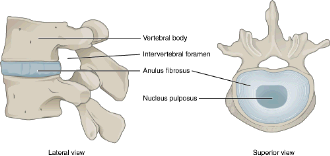

Les hernies discales sont très communes. Elles surviennent plus fréquemment chez des chiens de petite race d’âge moyen mais peuvent occasionnellement être vues chez des chiens de grande race et les chats. Il s’agit de la protrusion d’un disque intervertébral dans le canal vertébral comprimant ainsi la moelle épinière.